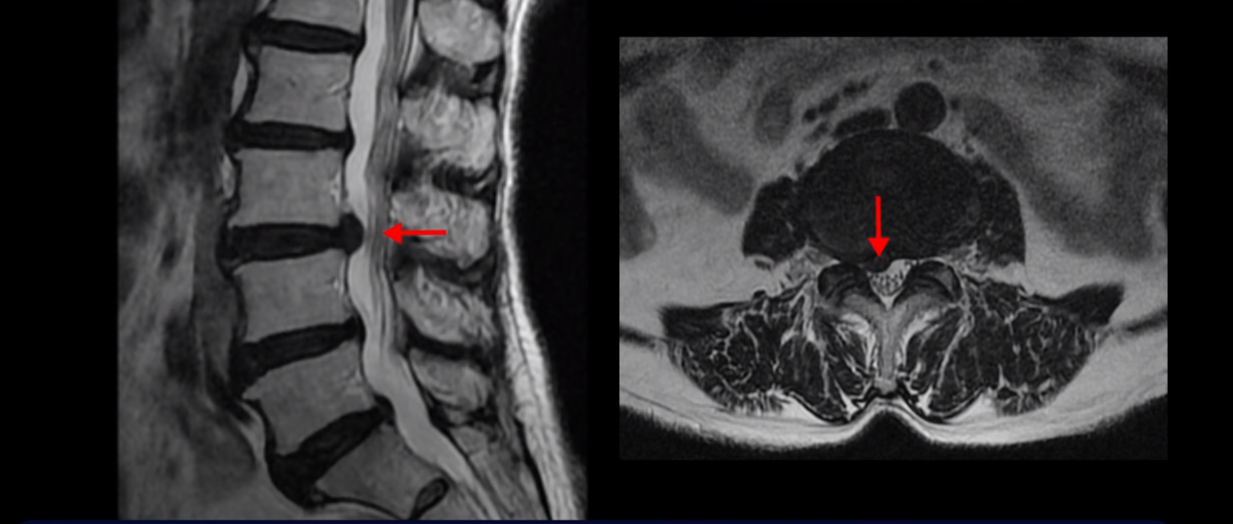

먼저 이분 MRI 보면서 간단히 설명 드린 후 어떻게 신경이 눌려서 수술해야 된다는 환자를 수술 없이 치료할 수 있는지 또 치료는 어떻게 하는지 자세히 설명 드리겠습니다. 이분 허리 MRI를 보면 여러 마디가 퇴행되어 있고

3번 4번 마디에 디스크 파열이 있습니다.

하지만 이 디스크 파열은 오래된 걸로 보이며, 지금 이 환자분의 아픈 양쪽 다리 특히 양쪽 발의 통증, 발 시린 증상과는 관련이 없어 보입니다. 오른쪽 왼쪽의 신경가지가 빠져나가는 추간공을 보면 오른쪽은 5번 1번과 4번 5번이 많이 좁아져 있고

왼쪽은 5번 1번이 많이 좁아져 있습니다.